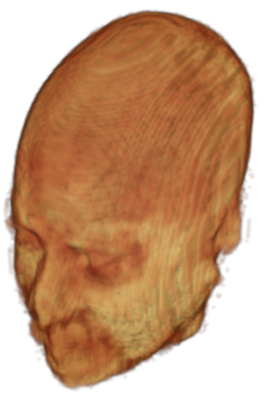

The digitalization of heath records has increased the risk of –and impact of– large scale data leaks. Although data compliance standards have been enacted to protect health records (HIPAA and GDPR), privacy of medical data is a growing concern. Three-dimensional scans such as magnetic resonance images (MRI) and computed tomography (CT), for example, contain an intrinsic privacy risk [Lotan et al.(2020)Lotan, Tschider, Sodickson, Caplan, Bruno, Zhang, and Lui]. Detailed renderings of the head can be crafted from 3D scans using techniques such as volumetric raycasting, as in Figure 1. This vulnerability can expose the patient’s identity if the renderings are matched to a face database [Mazura et al.(2012)Mazura, Juluru, Chen, Morgan, John, and Siegel, Lotan et al.(2020)Lotan, Tschider, Sodickson, Caplan, Bruno, Zhang, and Lui].

![]() |

Therefore, in this work, we define a new class of de-identification techniques that remodels the privacy-sensitive regions without altering the content of medically relevant data (see Figure 1). Under such a remodeling approach, the face, eyes, oral and nasal cavities, etc. should exhibit realistic appearance and structure of appropriate size, but should otherwise be independent of the original data. To solve this task, we propose a novel model called Convex Privacy GAN, or CP-GAN, that conditions on a convex hull of the skull extracted from the scan to be de-identified. The generator learns to synthesize volumes that preserve medically-sensitive regions such as the brain, while non-invertibly remodeling privacy-sensitive characteristics from the original scan.